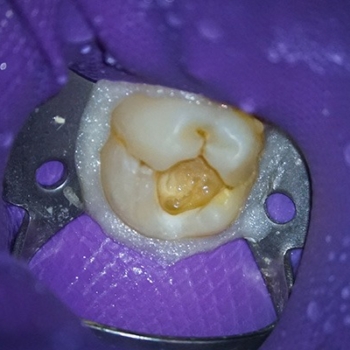

Complete sealing was achieved using a rubber dam, a stainless-steel Clamp, and a light-curing Flowable dam located around the clamp to prevent bacterial contamination of the area to be treated. The caries were removed circumferentially from the coronal towards the cervical margin to limit the movement of bacteria to the pulp tissue space (9). An exploration of the cavity preparation floor showed a pulp exposure (Figs 3 & 4). It is always advisable to explore the cavity preparation floor with an endo explorer, because smaller carious-exposed pulps may be overlooked.

Fig. 3. & Fig. 4. Pulp exposure at the level of the cavity preparation floor, with minimum hemorrhaging that was easy to control.